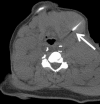

Purpose: To assess the feasibility of combined electromagnetic device tracking and computed tomography (CT)/ultrasonography (US)/fluorine 18 fluorodeoxyglucose (FDG) positron emission tomography (PET) fusion for real-time feedback during percutaneous and intraoperative biopsies and hepatic radiofrequency (RF) ablation.

Materials and methods: In this HIPAA-compliant, institutional review board-approved prospective study with written informed consent, 25 patients (17 men, eight women) underwent 33 percutaneous and three intraoperative biopsies of 36 FDG-avid targets between November 2007 and August 2010. One patient underwent biopsy and RF ablation of an FDG-avid hepatic focus. Targets demonstrated heterogeneous FDG uptake or were not well seen or were totally inapparent at conventional imaging. Preprocedural FDG PET scans were rigidly registered through a semiautomatic method to intraprocedural CT scans. Coaxial biopsy needle introducer tips and RF ablation electrode guider needle tips containing electromagnetic sensor coils were spatially tracked through an electromagnetic field generator. Real-time US scans were registered through a fiducial-based method, allowing US scans to be fused with intraprocedural CT and preacquired FDG PET scans. A visual display of US/CT image fusion with overlaid coregistered FDG PET targets was used for guidance; navigation software enabled real-time biopsy needle and needle electrode navigation and feedback.

Results: Successful fusion of real-time US to coregistered CT and FDG PET scans was achieved in all patients. Thirty-one of 36 biopsies were diagnostic (malignancy in 18 cases, benign processes in 13 cases). RF ablation resulted in resolution of targeted FDG avidity, with no local treatment failure during short follow-up (56 days).

Conclusion: Combined electromagnetic device tracking and image fusion with real-time feedback may facilitate biopsies and ablations of focal FDG PET abnormalities that would be challenging with conventional image guidance.